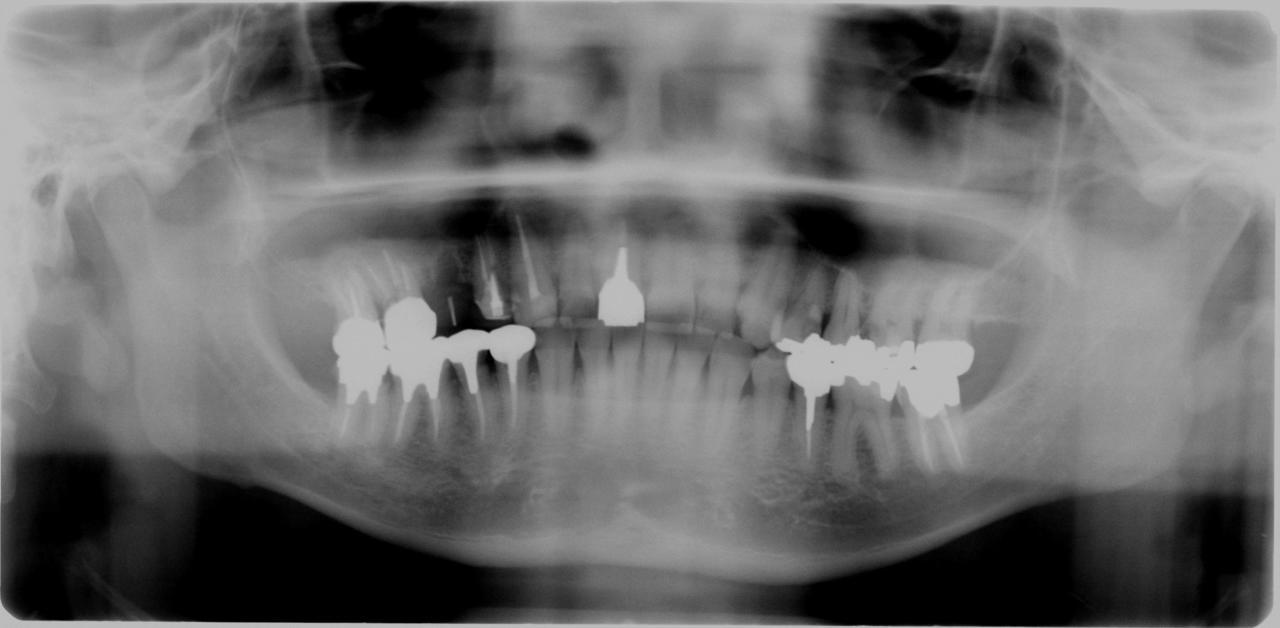

下顎臼歯部 3本インプラント埋入症例

症例 70代 男性

主訴 入れ歯からインプラントに変えたい

【術前レントゲン写真】      【術後レントゲン写真】

インプラント埋入手術費用

150000×3本=450000円+税